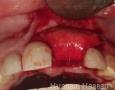

Pictures

Surgery

2 Months